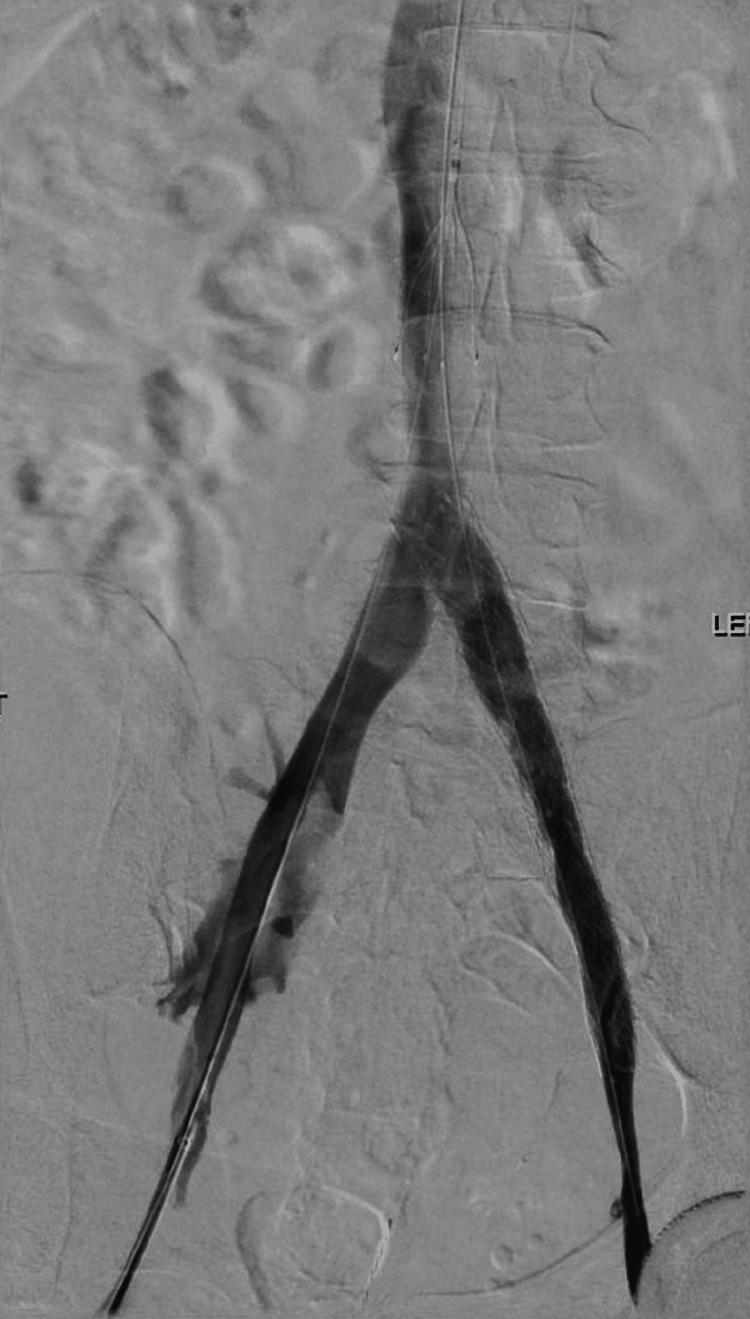

May-Thurner Syndrome (MTS) is a unique condition characterized by the compression of the left iliac vein by the right common iliac artery, which causes venous outflow obstruction and a high risk of venous sequelae. May-Thurner Syndrome is a condition that is primarily observed in females and is an uncommon cause of deep vein thrombosis (DVT). The more common presentation of DVT is in the lower left extremity, although there have been cases of right-sided formation. In this case report, we present a patient with unprovoked, recurrent, left-sided deep vein thrombosis in a 70-year-old woman. The aim of this case report is to highlight this uncommon condition and to suggest consideration of MTS in the setting of a patient with recurrent unprovoked DVTs of the same extremity.

梅-图二氏综合征(MTS)是一种独特的病症,其特征为右髂总动脉压迫左髂静脉,导致静脉流出道梗阻以及发生静脉后遗症的高风险。梅-图二氏综合征主要见于女性,是深静脉血栓形成(DVT)的一种罕见病因。DVT更常见的表现是在左下肢,不过也有右侧形成的病例。在本病例报告中,我们介绍了一名70岁女性患者,其出现不明原因的、复发性左侧深静脉血栓形成。本病例报告的目的是强调这种罕见病症,并建议在同一肢体反复出现不明原因DVT的患者中考虑梅-图二氏综合征。